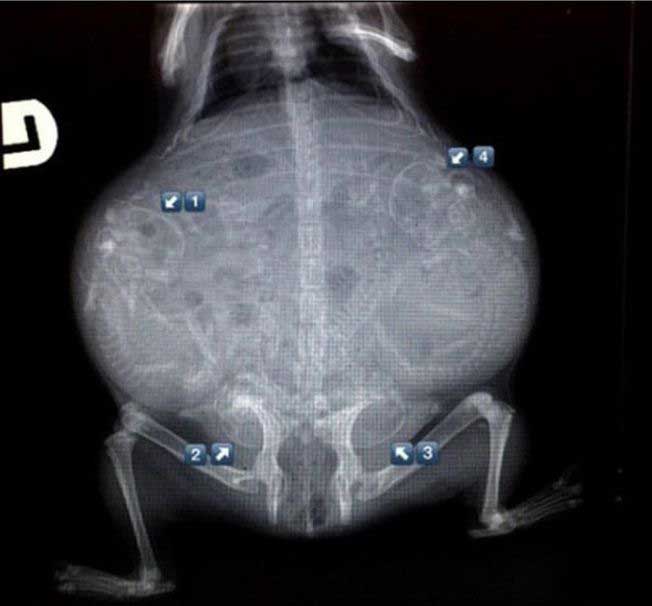

妊娠した様々な動物たちをレントゲン(X線)写真で見てみたギャラリー。サメ、ネズミ、犬、猫など。一度に複数の子供を出産する犬や猫などは特に怖い事に…。

4. イヌ